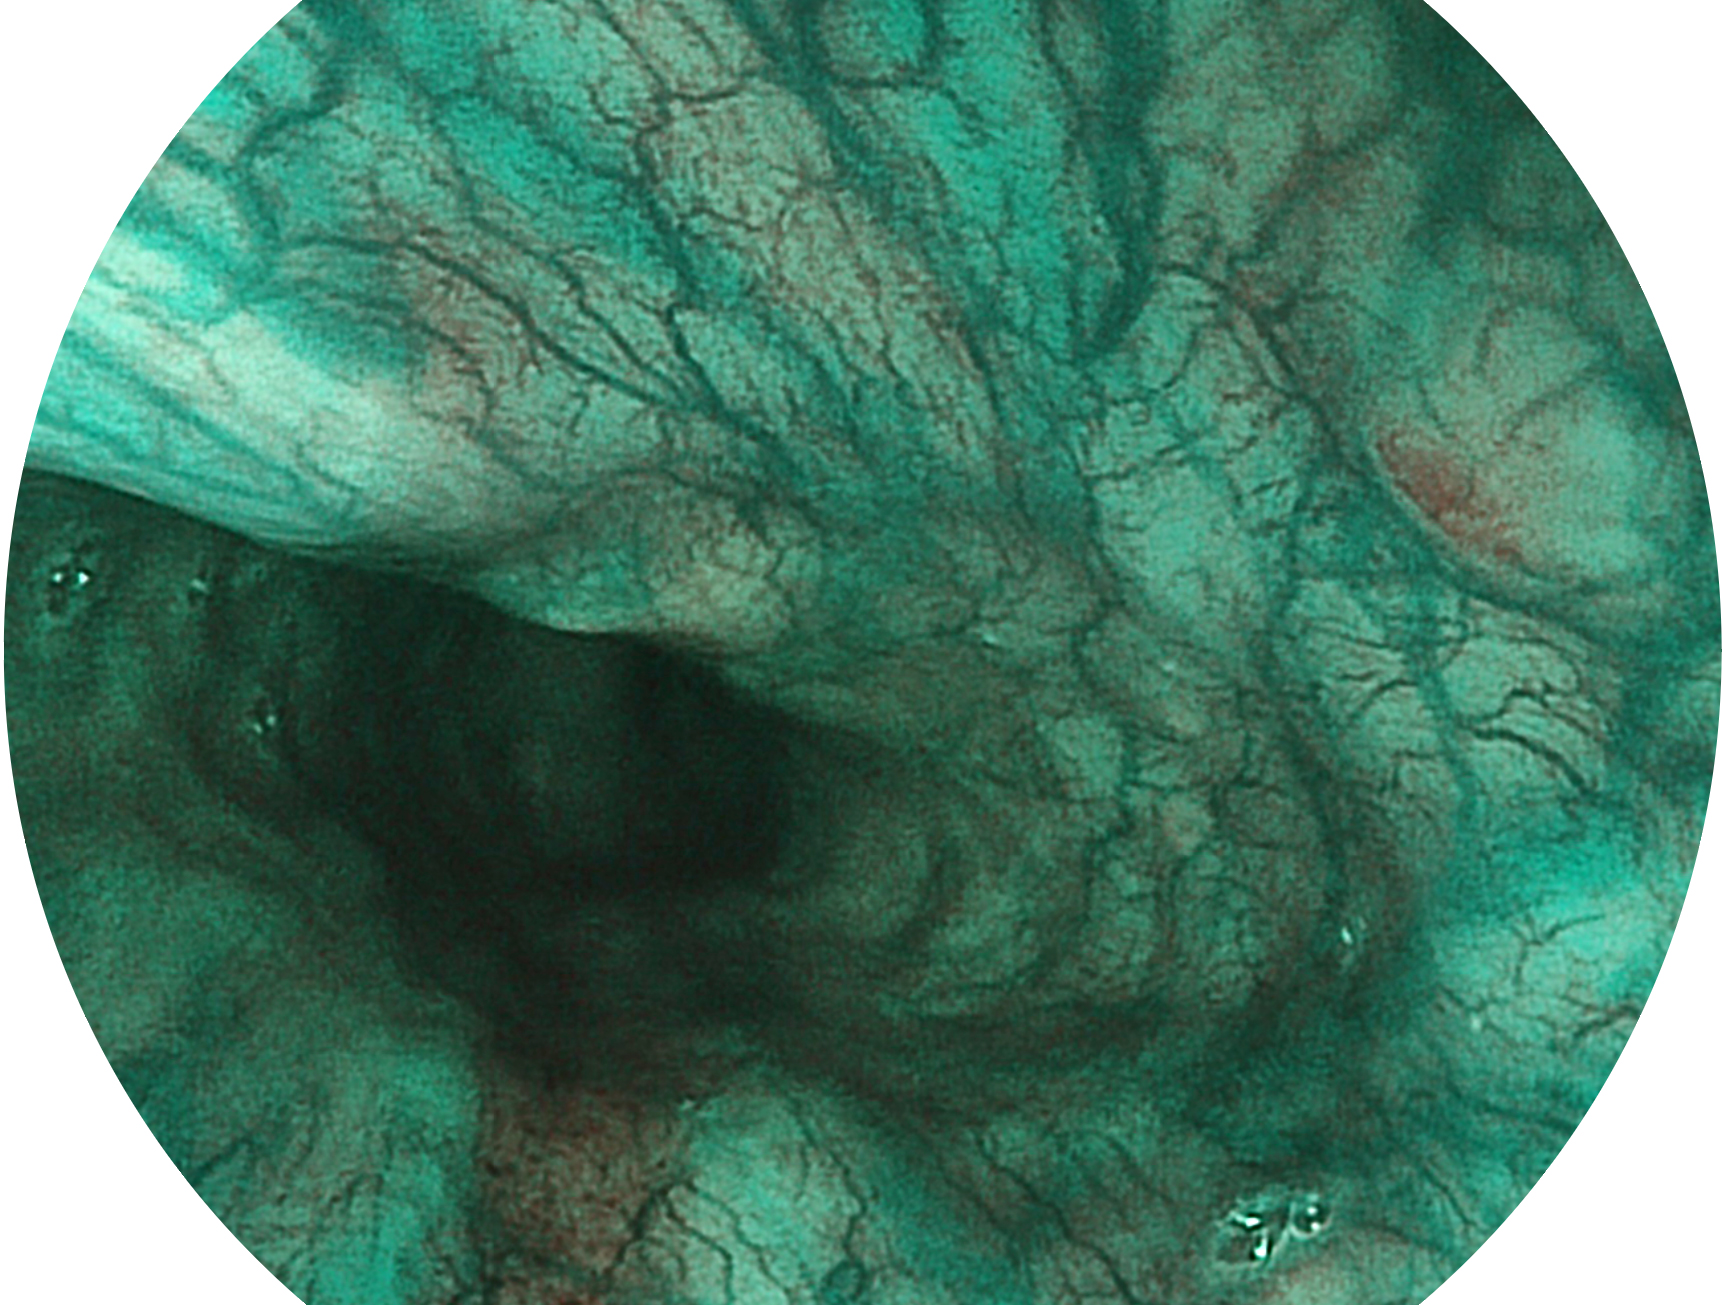

与上一代VIST相比,摒弃了滤光转轮而直接采用光谱组合的方案,加入了血红蛋白吸收高峰与次高峰的蓝紫光和绿光光谱,更有利于黏膜血管吸收,突显浅表层血管和中层血管的对比度,因而具备更高的图像对比度,近景观察时,有助于微细结构变化及病灶边界的观察。

• 白光图像 VIST图像